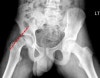

초기 영상검사는 AP, Pelvis Frog legs이며, AP에서는 영상소견이 미미해 감지하기가 힘듭니다.

탈구는 초기에는 후방으로 발생해 frog’s leg lateral view가 필수적이고 75%의 환자가 의미 있는 내측 탈구를 보입니다.

X-ray : Klein line

대퇴골경부의 상단 외측면을 따라 연결한 선 (Klein line)이 대퇴골두를 지나가지 않게 됩니다(Trethowan‘s sign).

CT, MRI은 골단의 이동을 알기쉬워 조기진단에 유리합니다.